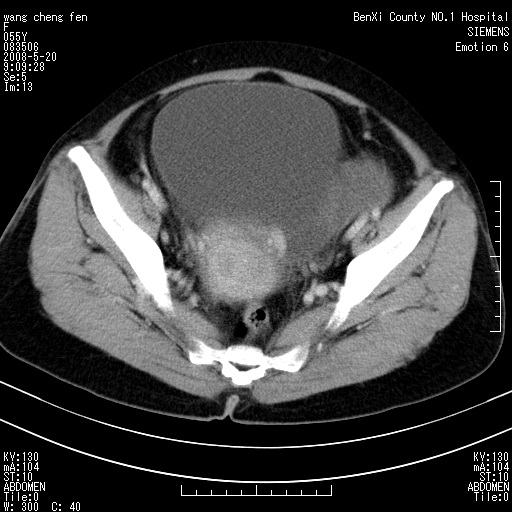

女、绝经后阴道流血3个月

左侧附件区可见一囊性占位,边缘清楚,内可见不规则形软组织影 ce:囊壁及内部可见强化 考虑 卵巢囊腺瘤

左侧附件区巨大囊实性病灶,边缘光整,病灶囊壁较厚,增强示囊壁及实性部分明显强化,强化呈度与宫体实质大致相同,宫腔积液征像,未见盆腔积液等其他异常,考虑左侧卵巢囊腺癌,不除外囊腺瘤及浆膜下肌瘤坏死

左侧附件区巨大囊实性病灶,边缘光整,病灶囊壁较厚,增强示囊壁及实性部分明显强化,强化呈度与宫体实质大致相同,宫腔积液征像,未见盆腔积液等其他异常。绝经后阴道流血3个月,结合病史左侧卵巢囊腺癌首先考虑,宫腔扩大不除外累及。期待结果。

支持浆膜下子宫肌瘤.之前由于网络原因未看全图片,现在重看,宫颈见一类圆形低密度影,增强轻度强化,低于肌层强化,宫腔扩大,考虑宫颈癌伴宫腔积液可能性大.